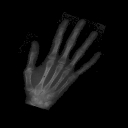

In the second example, see Fig. 4, we compare the behaviour of the SSD and the NCC-based distance. The example consists of two different hands which, in addition, are rotated relative to each other. Here, the deformation is much larger than in the previous example, but still fairly regular. The data was generated similarly to the previous example, but with only five angles from the interval degrees. Note also that the intensities of the template and target image are different (roughly by a factor of two). First, we discuss the transport equation. The intensity difference is a serious issue if we use the SSD distance, as we can see in Fig. 4(e). The hand is deformed into a smaller version in order to compensate the differences. If we use the NCC-based distance instead, which can deal with such discrepancies, the result is much better from a visual point of view. The shapes are well-aligned. The resulting SSIM value is still low, which is not surprising since SSIM is not invariant with respect to intensity differences between perfectly aligned images. However, neither of the two approaches is able to remove or create any of the additional (noise) structures in the images. For the combination SSD with continuity equation, no satisfactory results could be obtained. Since no change of intensity is possible by changing the size of the hand, part of it is moved outside of the image. This behaviour could potentially be corrected if other boundary conditions are used in the implementation. Therefore, we do not provide an example image for this case. Using the NCC-based distance, the results look similar as for the transport equation with slightly worse SSIM value. These results suggest that the NCC-based distance is a more robust choice that avoids unnatural deformations, which would be required in the case of SSD to compensate intensity differences. In this example, the computation time was between 50 and 325 seconds.